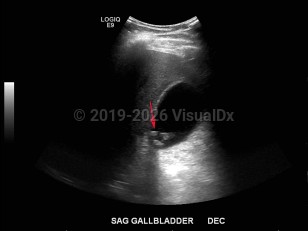

Biliary calculus